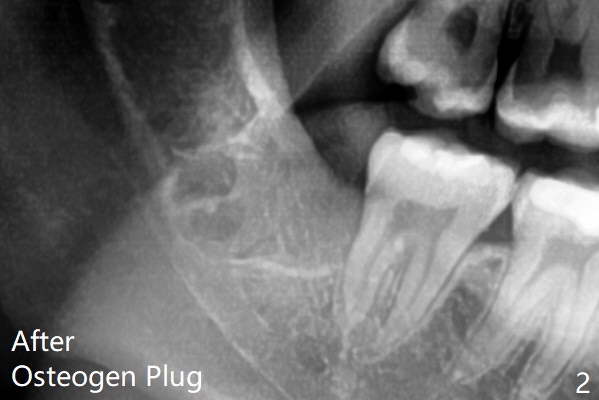

The lower 3rd molar sockets heal in 14 months (Fgi.3).